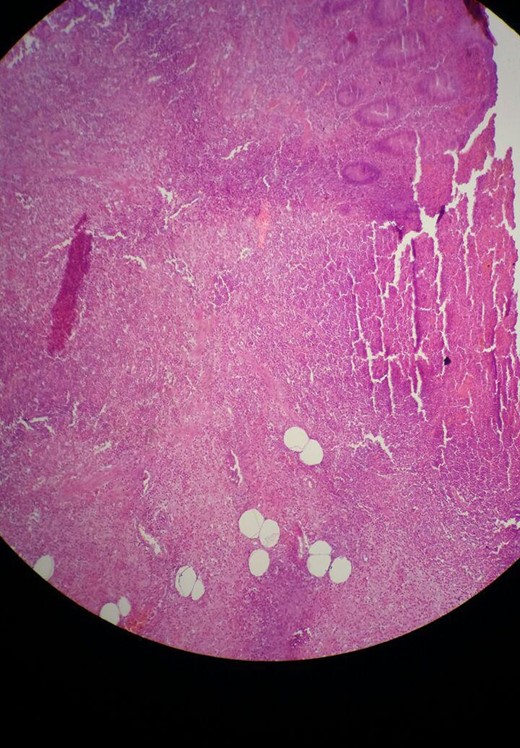

A 30-year-old female presented to the emergency department complaining of abdominal pain. The pain started 48 h ago diffusely in the umbilical region and subsequently migrated to the right iliac fossa. She had associated nausea, vomiting and loss of appetite. There was no alteration in bowel habits. The patient was otherwise healthy and has not undergone any previous abdominal or pelvic surgeries. On physical examination the patient was febrile (39°C) and tachycardic. Examination of the abdomen revealed localized tenderness as well as rebound tenderness at the McBurney point in the right iliac fossa. Laboratory findings showed severe leukocytosis (22 000/ul) with a left shift (neutrophils 88%), and increased C reactive protein (100 mg/dl). Urinalysis did not reveal any specific findings and urine pregnancy test was negative. Abdominal ultrasonography was performed and revealed an appendiceal shield, free fluid, and abscess formation in the right iliac fossa. A definite diagnosis of acute appendicitis was made based on Alvarado score of (10) and a decision was made to perform an open appendectomy via a Rocky Davis incision. Intraoperative findings showed a small quantity of free fluid in the abdomen and two appendices lying on either side of the ileocecal valve, one of them was swollen and erythematous (Fig. 1). The surgeon resected the two appendices. Histopathological examination confirmed the diagnosis of appendiceal duplication. The first specimen showed an inflamed appendix with lymphoid hyperplasia, thickened muscularis and prominent neutrophilic infiltration compatible with acute appendicitis (Fig. 2). The second specimen showed a normal appendix without serosal inflammation, or neutrophilic infiltrate in the muscularis propria (Fig. 3). The tip was present without any lesions. The patient had a full recovery without postoperative complications and was discharged on the third postoperative day.

Microscopic view of the first specimen with acute appendicitis. Sections show focal ulceration of the mucosa and acute inflammatory infiltrate (mainly neutrophils) throughout the wall.